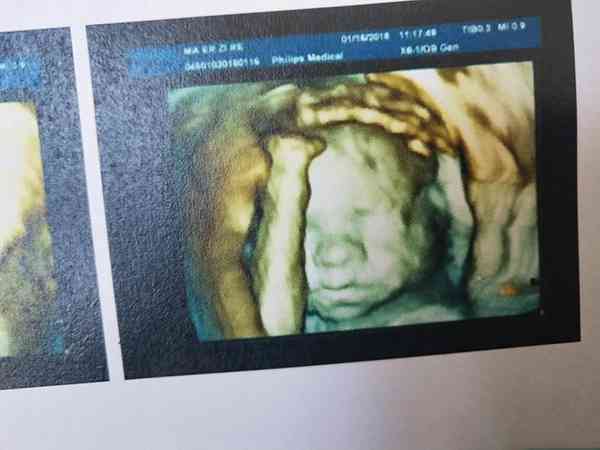

网上传看四维彩超单上的Qualhigh数值、字体颜色、图像形状就能准确看男女,这个说法其实是没有任何科学依据的。我国是禁止进行医学性别判断的,除非有跟性别先关的遗传性疾病,所以四维彩超单上是不会做出任何有关男女性别的判断。家长们想要知道胎儿是男是女只能通过四维彩超的图像去分别胎儿生殖器进行判断,一般24周胎儿生殖器已有明显区别,如果运气好是可以看出来的。

四维彩超跟其他超声检查相比,可以实时观察人体内部器官的动态运动,当然也能准确地看出胎儿生殖器官是什么样,从而判定胎儿的性别。但由于我国明令禁止胎儿性别判断。所以网上不少人就开始用自己猜测的方法进行判断,其实大多都是没有任何可信度的,但如果家长们好奇也是可以试试的,但不要信以为真。具体判断方法如下: